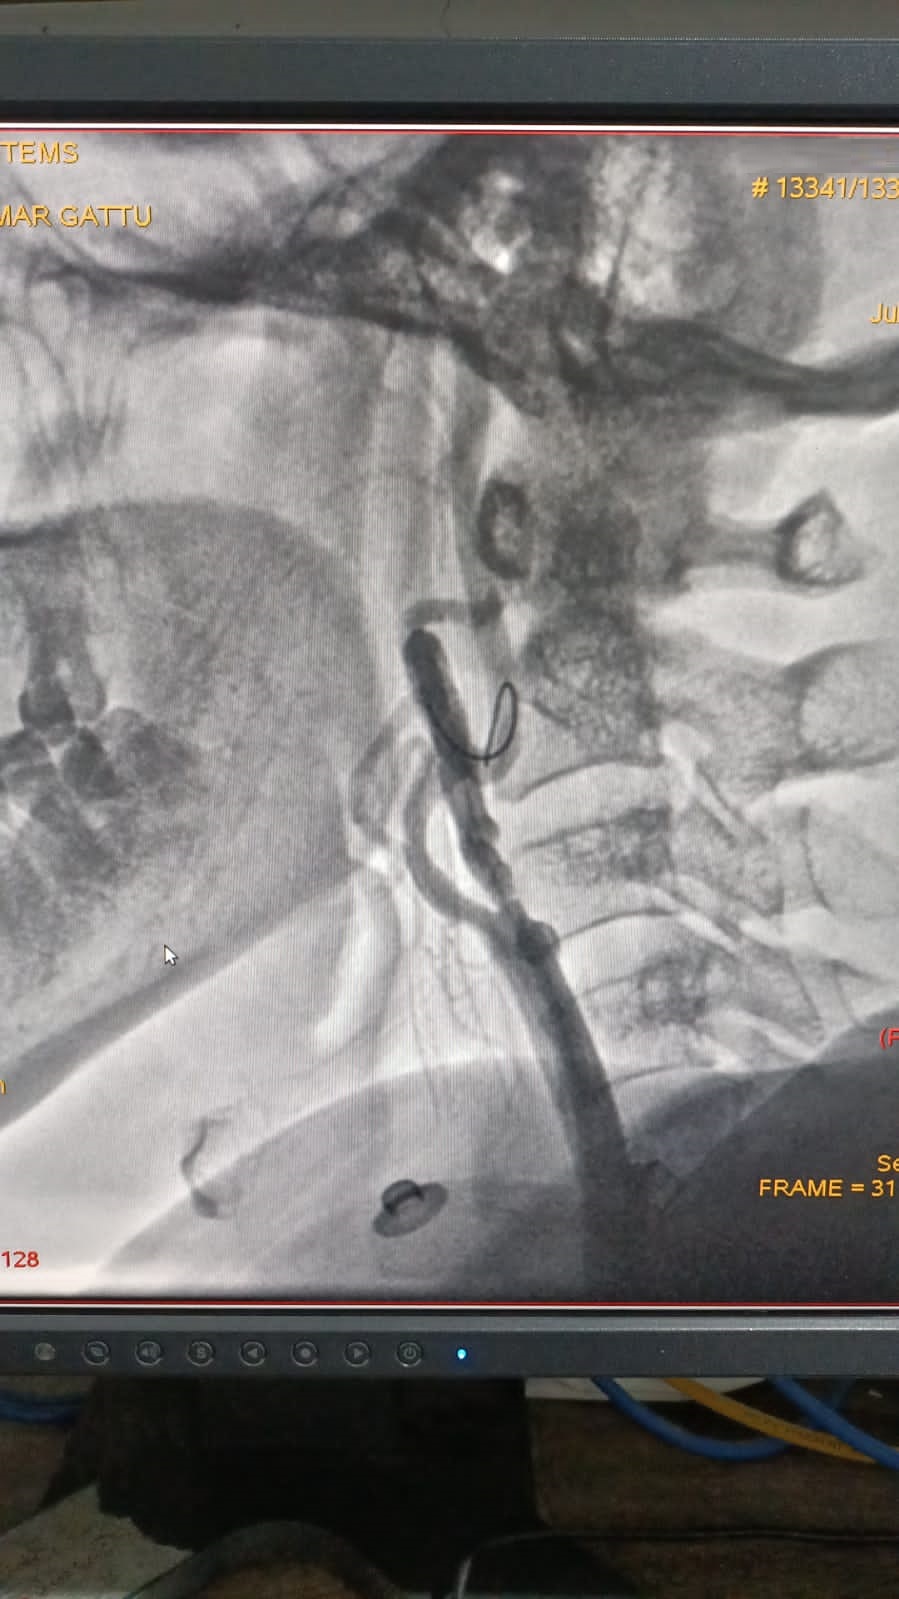

Right Coronary Diseased Artery